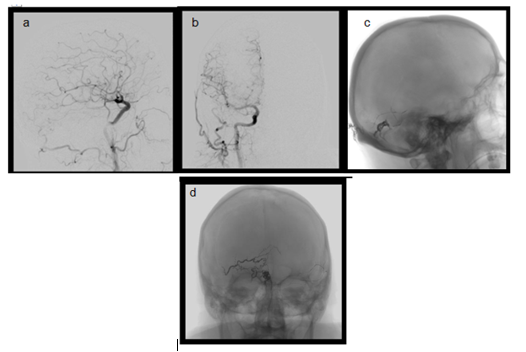

Patient was sedated, paralysed and intubated. Femoral artery was catheterised on the left side and a four vessel brain angiography was obtained. A tentorial dural fistula was diagnosed. There were several distended tortuous veins depicting venous outflow hypertension. We proceeded with transarterial embolization of the feeding arteries using ONYX [5-8]. Patient remained stable throughout the procedure (Figure 2b&3).

Figure 3 a) Post embolisation Lateral projection after infusion from right CCA. b) A-P projection after infusion right CCA. c) Lateral X-Ray depicted ONYX inside the fistula. d) A-P view depicting ONYX inside the fistula.